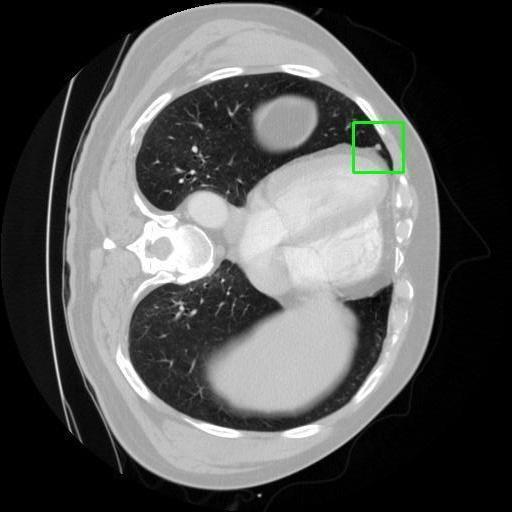

We developed an AI-based system using deep learning models for analyzing lung CT scans to detect and classify pulmonary nodules. We chose the YOLOv11 architecture for its enhanced object detection capability and adapted it specifically for medical imaging, incorporating pixel-level precision and severity classification.

Classification into three severity levels with colored bounding boxes.

Successfully built and deployed an AI model (YOLOv11) capable of detecting lung nodules in CT scans with high accuracy and real-time performance.

Designed a severity classification system that categorizes nodules into null, moderate, and severe using colored bounding boxes, assisting in rapid clinical decision-making.

Real-world medical image processing needs 3D context awareness which 2D models like YOLO must adapt for.